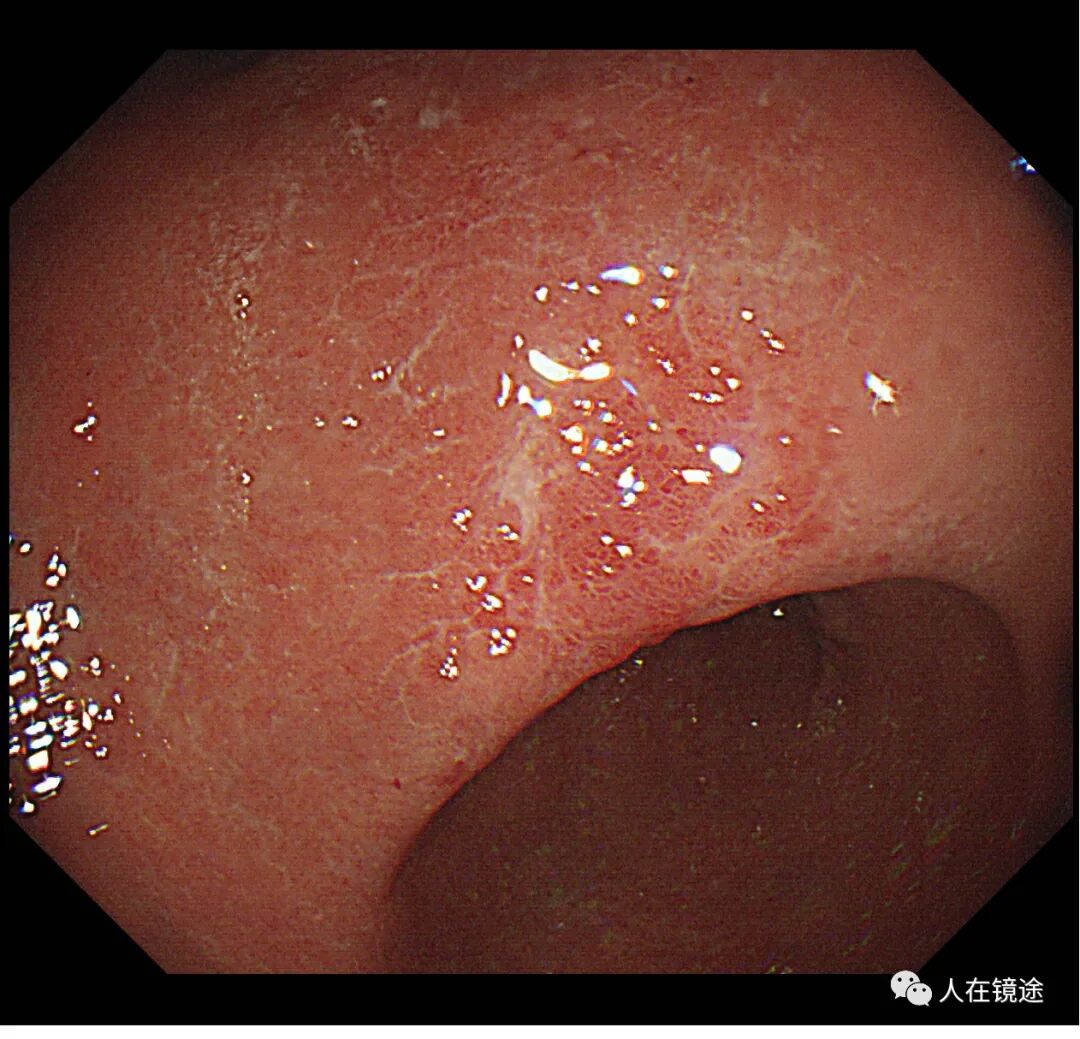

患者某某,女性,59岁,无症状胃镜检查示胃窦小弯见一0.8*1.2cmIIa粘膜发红病变,表面粗糙。

白光示胃窦粘膜红白相间,以白为主,胃窦小弯见一0.8*1.2cmIIa粘膜发红病变,表面粗糙。电子胃镜镜是什么奥林巴斯HQ290电子胃镜诊断胃窦早癌一例分享_https://www.jmylbn.com_新闻资讯_第3张

白光示胃窦小弯见一0.8*1.2cmIIa粘膜发红病变,表面粗糙